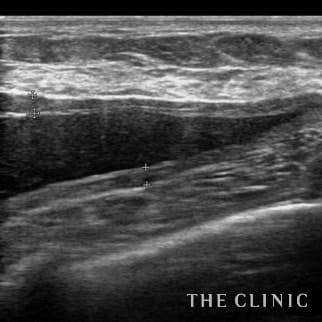

乳腺専用エコーを導入

術前後にエコー検査を行い、手術計画や結果についてを専門的に判断します。